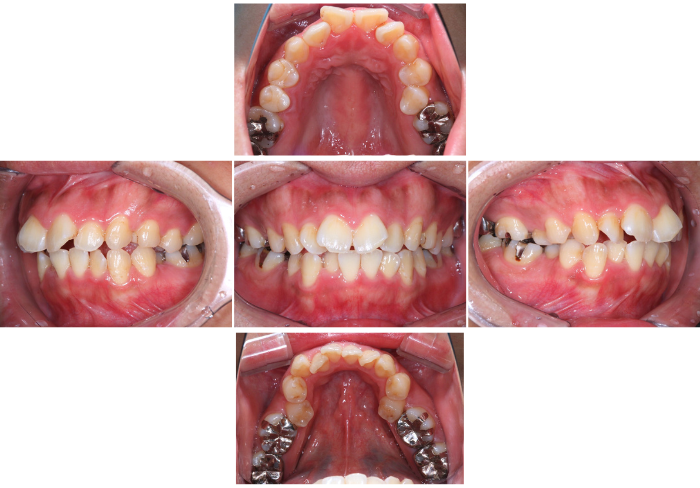

矯正歯科

24.05.22

矯正治療(ワイヤーを用いています)